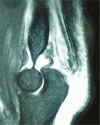

Distal triceps ruptures are rare injuries due to the special anatomical features of the muscle and tendon-bone junction.This injury typically occurs at the tendon-bone junction due to an eccentric contraction of the muscle.The treatment is controversial, especially in partial ruptures; surgical repair is indicated for complete ruptures of the distal triceps tendon.Several repair techniques have been described for acute complete ruptures.Chronic ruptures often require reconstruction rather than direct repair. Cite this article: Demirhan M, Ersen A. Distal triceps ruptures. EFORT Open Rev 2016;1:255-259. DOI: 10.1302/2058-5241.1.000038.